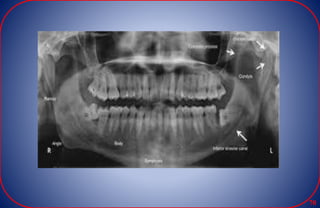

RADIOGRAPHIC LANDMARKS OF

MAXILLA

• Nasal fossa – The nasal fossae

are the nasal openings located

• Inferior nasal concha –

from the lateral walls of

the nasal cavity.

• Incisive foramen –

The foramen is the

termination of the

canal.

• Maxillary sinus – paired

paranasal sinuses.

• Zygomatic process -

U-shaped structure.

zygomatic bone attaches

to the maxilla.